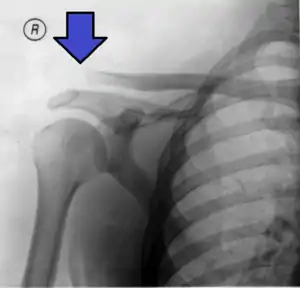

An Xray showing a separated shoulder. Notice the separation between the end of the collarbone and the scapula.

X-ray indicates a separated shoulder when the acromioclavicular joint space is widened (it is normally 5 to 8 mm).[8]